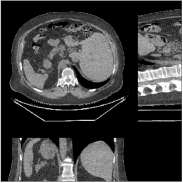

We evaluate the behavior of the PWLS-ULTRA method (with ) for 3D cone-beam CT data with . Fig.Β 2 shows the central slices along three directions for the underlying (true) XCAT phantom volume. We reconstruct the volume from low-dose CT measurements. Fig.Β 2 shows the RMSE and SSIM of PWLS-ULTRA for various choices of , the number of clusters (patch size and patch stride ). Rich models (large ) produce better reconstructions compared to using a single ST (). For the piece-wise constant phantom, clusters works well enough, with only a small additional RMSE or SSIM improvement observed for larger . Larger values of led to sharper image edges.

Fig.Β 5 shows the reconstructions and the corresponding error (magnitudes) images (shown for the central axial, sagittal, and coronal planes) for FDK, PWLS-EP, and PWLS-ULTRA () with the patch-based weights. Compared to FDK and PWLS-EP, PWLS-ULTRA significantly improves image quality by reducing noise and preserving structural details (see zoom-ins). Fig.Β 6 shows the RMSE for each axial slice in the PWLS-EP and PWLS-ULTRA (with the weights ) reconstructions. PWLS-ULTRA clearly provides large improvements in RMSE for many slices, with greater improvements near the central slice.